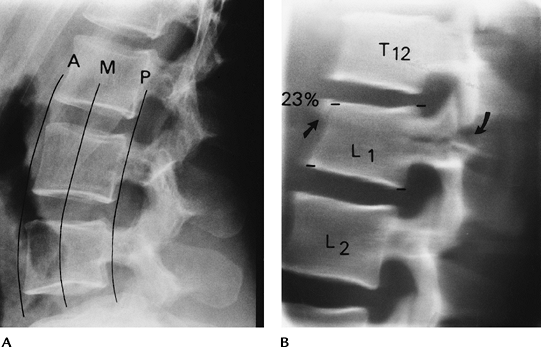

![]() |

FIGURE 3-27 Anterior wedge fractures. Normal anterior and posterior cortical lines of the lumbar (A) and thoracic (B)

vertebral bodies. The lumbar vertebral body is concave anteriorly and posteriorly, and the thoracic vertebral body is concave anteriorly and straight posteriorly. Lateral radiographs of mild anterior wedge fractures of T3 and T4 (C) and T12–L2 (D). Note the anterior buckling of the cortex in (D) (arrowheads). |